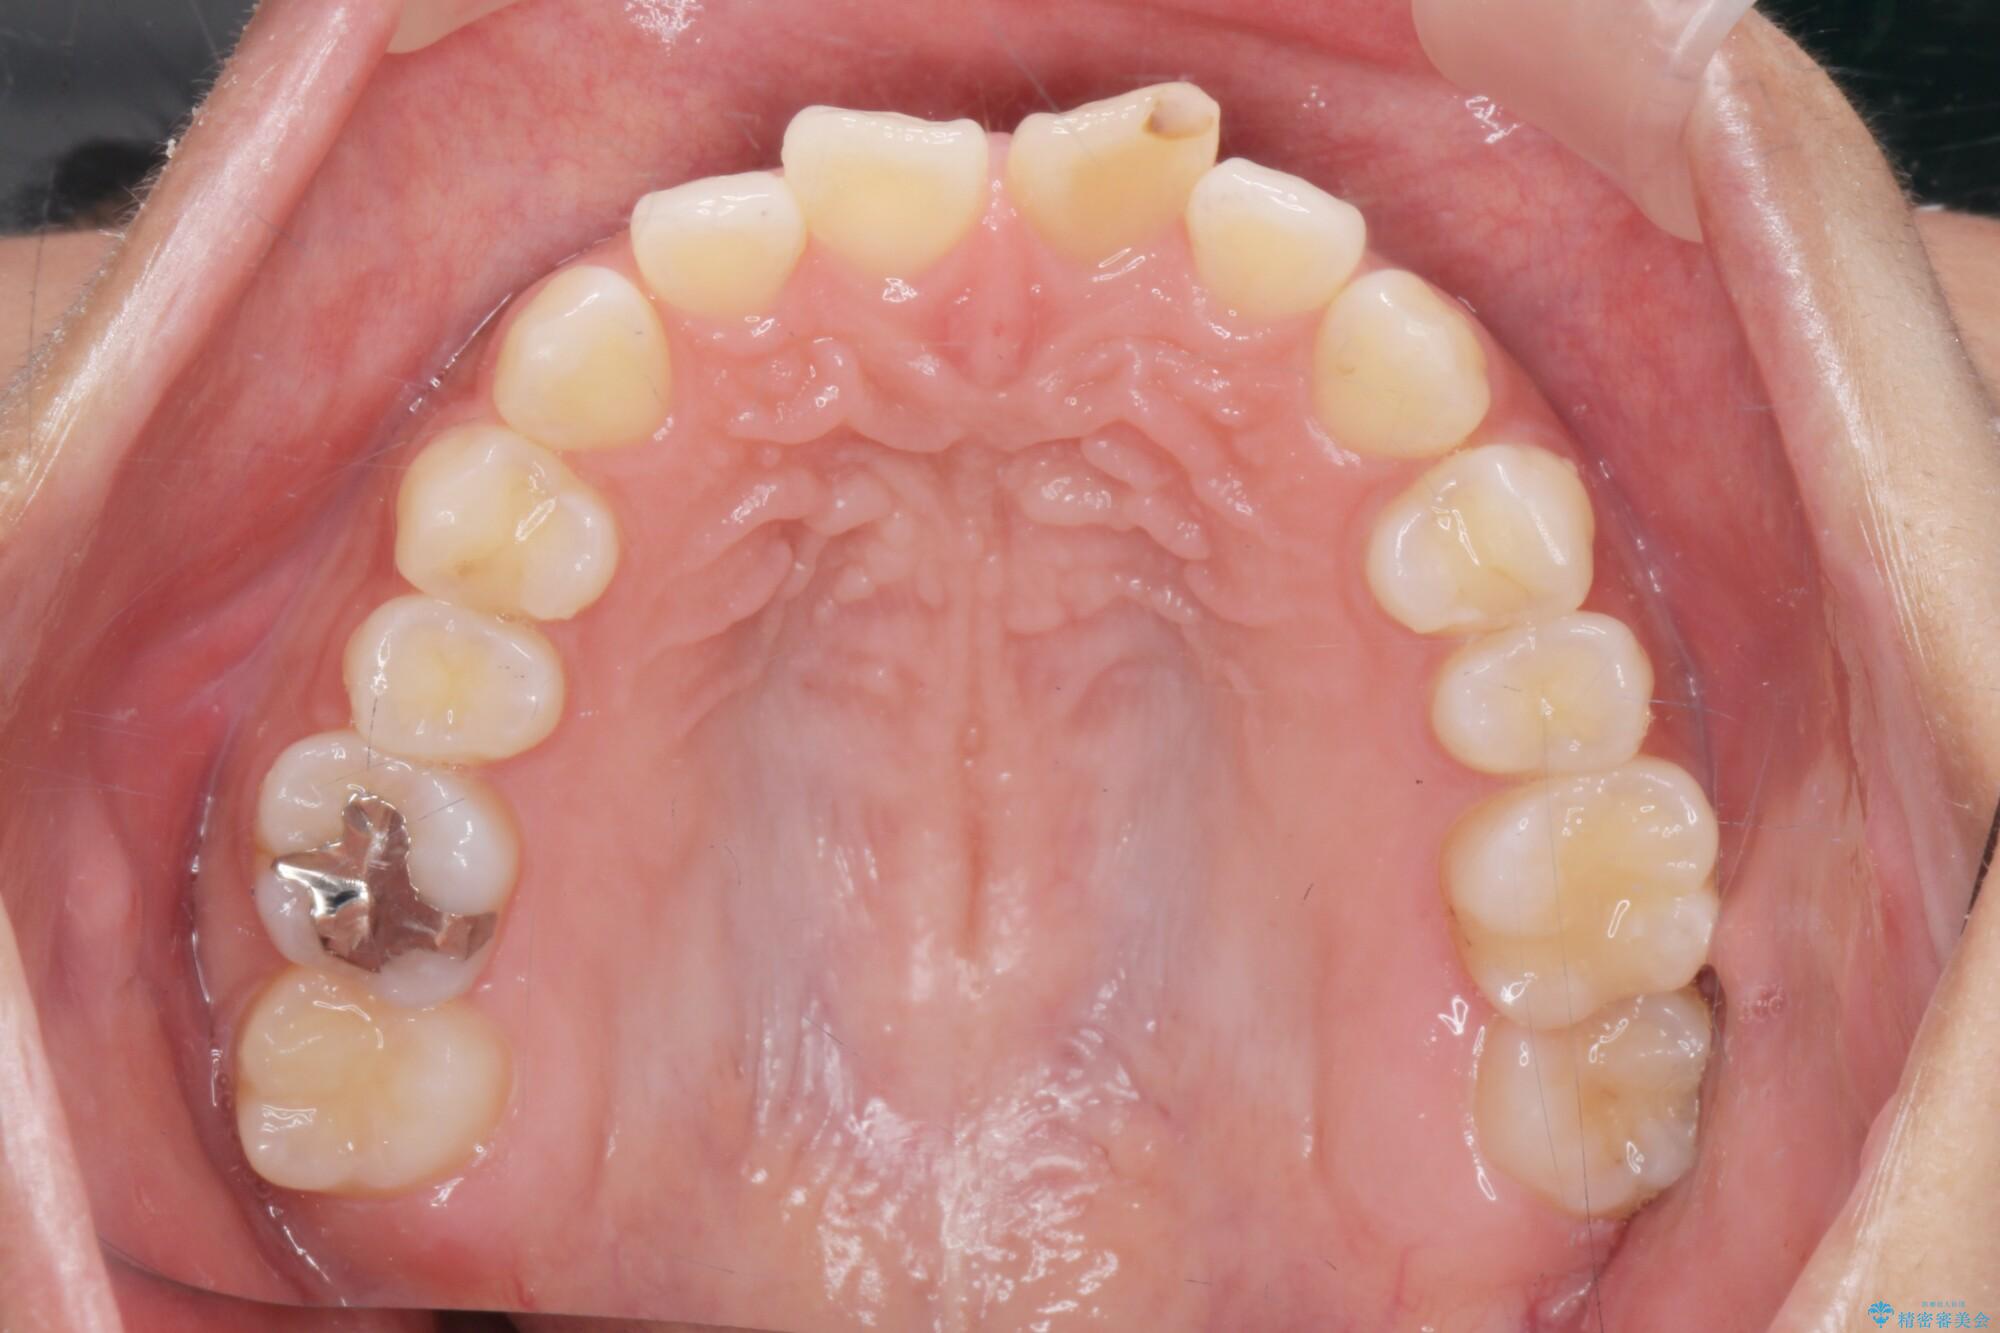

噛まない前歯と捻じれてしまった歯を改善したいと、矯正治療を希望された患者様です。

治療計画

仕上がりにこだわりたいと、装置はマウスピースではなくワイヤーを希望されました。

マルチブラケットを用いた非抜歯のワイヤー矯正で噛み合わせと歯並びを改善していきます。